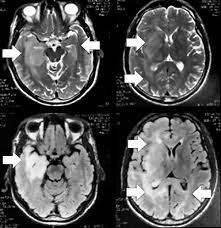

RM sugestiva de encefalite autoimune

Hipersinal em T2/FLAIR no lobo temporal medial bilateral + hipocampo → áreas multifocais corticais/substância branca → desmielinização/inflamação